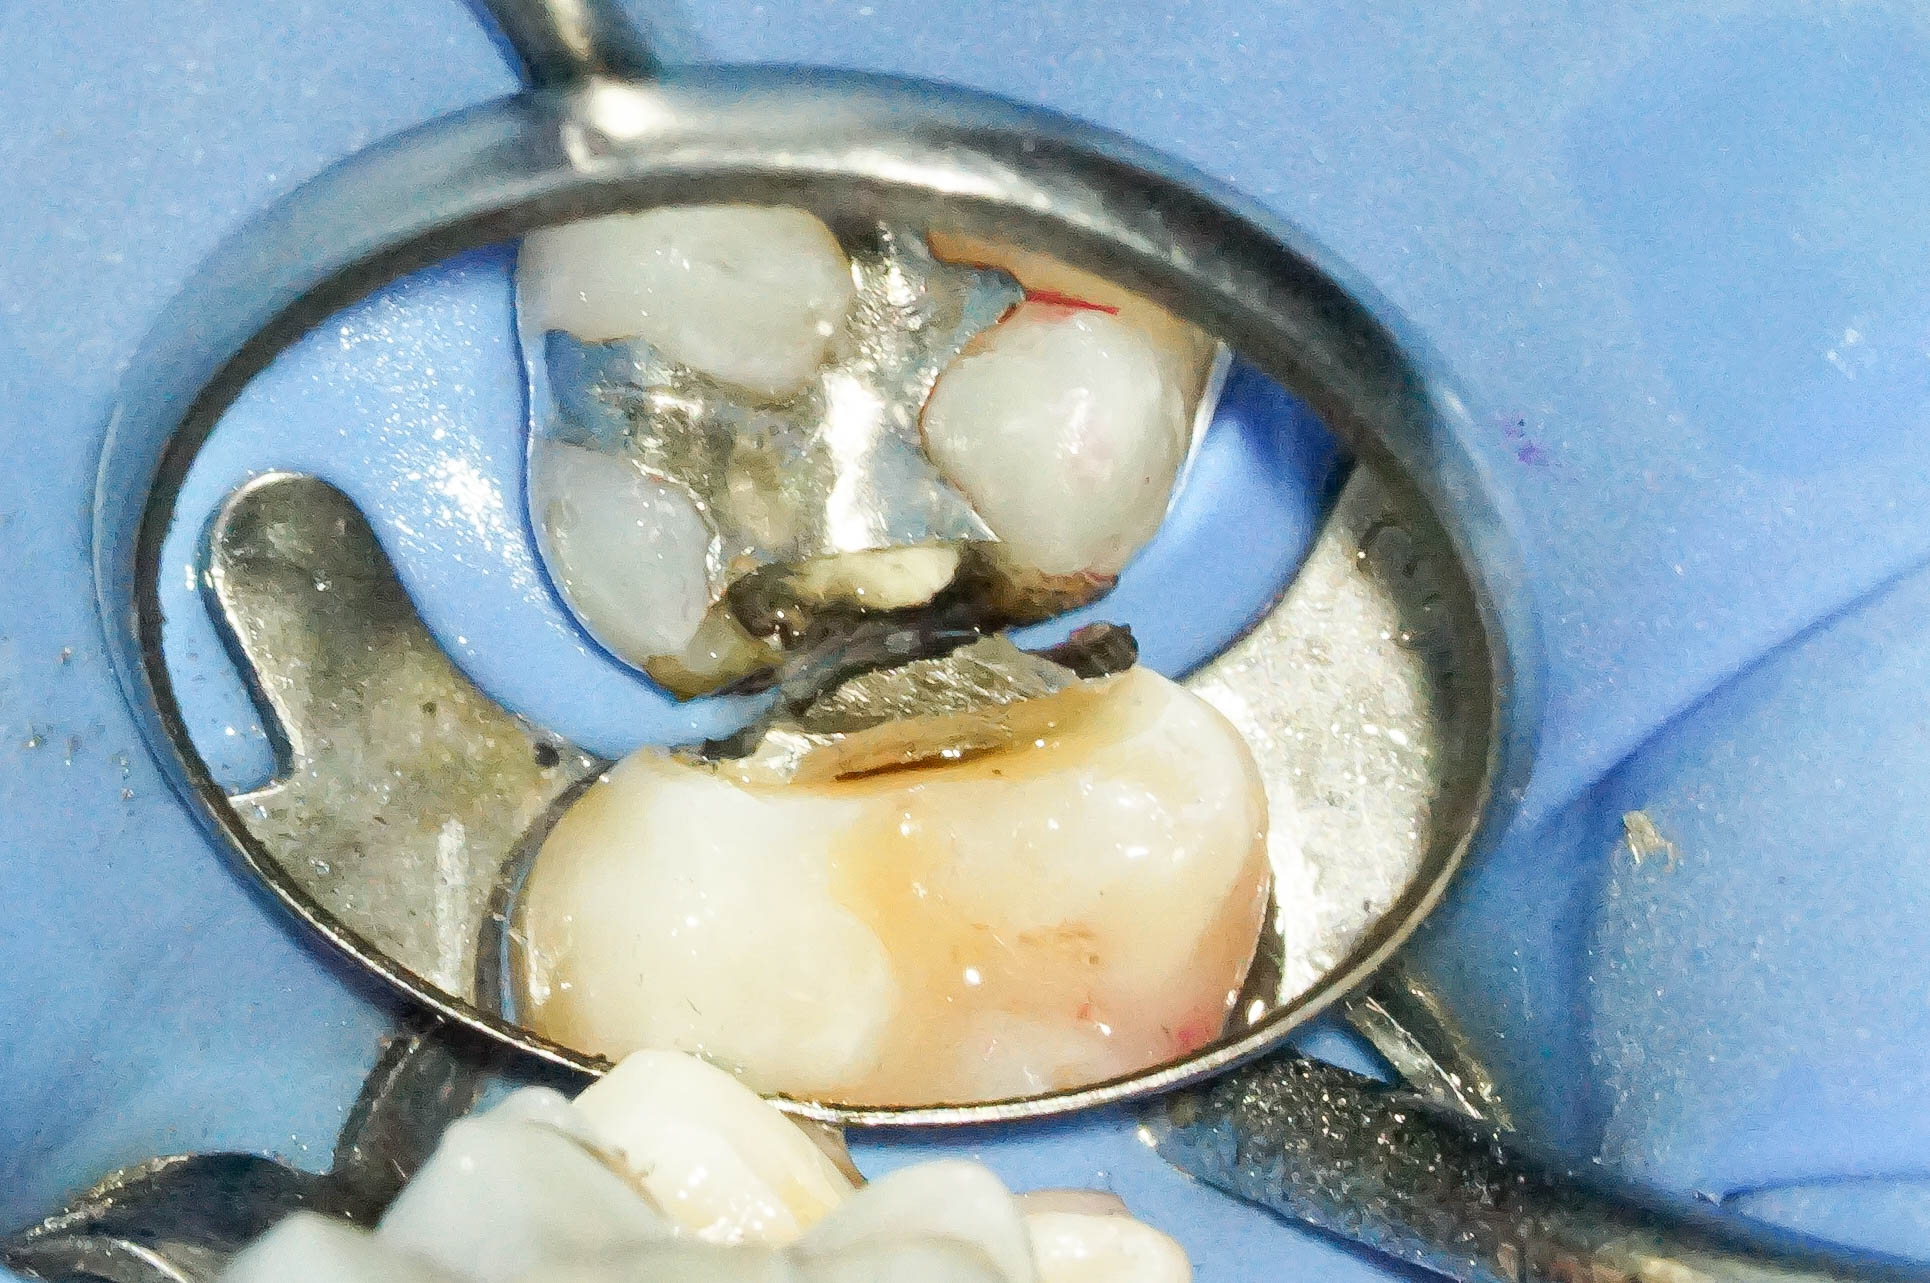

歯肉縁下ダイレクトボンディングを行った症例治療方法03

写真では分かりづらいですが、歯肉に隠れている部分に大きめのウ蝕が広がっていたので歯周外科処置を行い、視野を確保します。

レーザーで歯肉を焼き切って治療をする方法もありますが、レーザーで焼いてしまうと大きな歯肉退縮を引き起こします。

※画像はモノクロ加工しています。

歯肉縁下ダイレクトボンディングを行った症例治療方法04

歯周外科を行うことでウ蝕部分をしっかりと明示できるので、ウ蝕の取り残しをなくすことができます。

そして難易度は高いですが、その部位にラバーダムを設置します。

ラバーダムがなければ処置部位は血まみれ、唾液まみれで繊細な治療ができません。